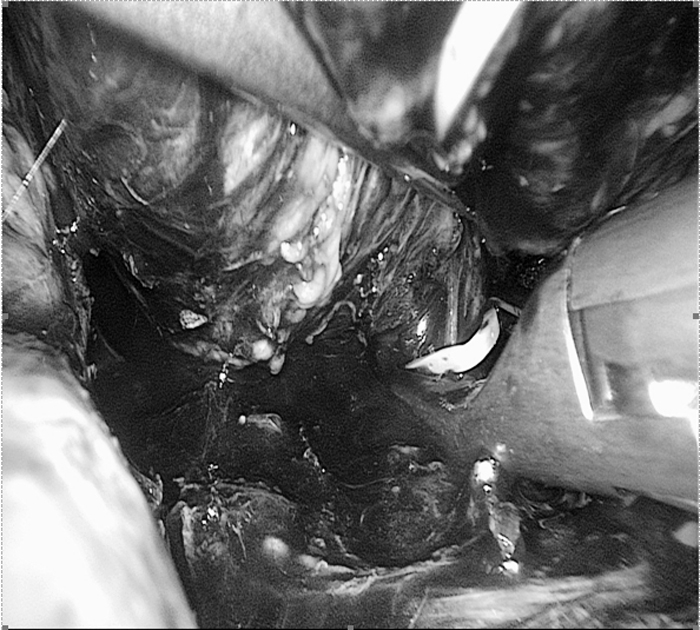

手術(shù)中影像(圖片已做處理)

??? 萬里軍仔細(xì)看了CT和磁共振片后,認(rèn)為腫瘤與腎靜脈、腹主動脈關(guān)系密切,建議用衢州市人民醫(yī)院最新引進(jìn)的320排螺旋CT做個(gè)血管成像,明確腫瘤與這些重要血管的關(guān)系。同時(shí)啟動了多學(xué)科會診治療(MDT)程序,邀請呼吸內(nèi)科、心血管內(nèi)科、內(nèi)分泌科、麻醉科、重癥醫(yī)學(xué)科、輸血科等相關(guān)科室進(jìn)行會診,充分估計(jì)術(shù)前、術(shù)中和術(shù)后可能遇到的問題,制定了幾套方案。與患者及家屬進(jìn)行溝通,獲得他們的配合信任。

??? 麻醉科余功敏主任醫(yī)師已經(jīng)和萬醫(yī)生配合完成了好幾臺嗜鉻細(xì)胞瘤的手術(shù)。手術(shù)當(dāng)日,余功敏在完成了深靜脈穿刺、動脈穿刺和氣管插管后,又在一旁準(zhǔn)備了自體血回輸設(shè)備,說:“你放心開始手術(shù)吧!”術(shù)中雖然經(jīng)歷了血壓飆升和血壓下降,但余功敏鎮(zhèn)定自若,降壓藥和升壓藥輪流上陣。經(jīng)過嚴(yán)密的麻醉監(jiān)護(hù)、精確的術(shù)中操作,一個(gè)小時(shí)后在腹腔鏡下有驚無險(xiǎn)地順利切除腫瘤。手術(shù)順利,老太太術(shù)后恢復(fù)快,第五天就出院。